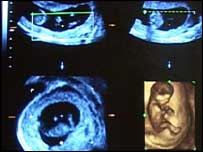

A televisão da Grã-Bretanha transmitiu, nesta terça-feira, um polêmico documentário mostrando uma mulher fazendo um aborto. O programa, o primeiro com esse tipo de imagens exibido na TV do país, incluiu uma cena de uma bomba de sucção usada nos abortos. O aborto filmado foi feito em uma clínica londrina, e a mulher não foi identificada. Foram mostradas também imagens de fetos abortados em diferentes períodos, de sete a 21 semanas de gravidez. Idades diferentes O documentário dirigido por Julia Black, chamado My Foetus (Meu Feto) foi ao ar pelo canal Channel 4. A diretora disse esperar que ele gere um debate no país. "O tema ainda é tabu e não é discutido abertamente. Pensei, então, que deveríamos mostrar as imagens", disse ela. Grupos contrários e a favor do aborto questionaram a validade do documentário e o uso de imagens de fetos abortados.